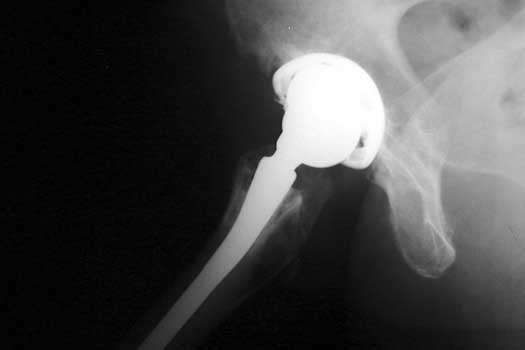

Polyethylene Liner Wear

• Liner thinning related to chronic wear

• Occurs in superior aspect, along biomechanical vector of force

• Radiographic features

• Femoral head component eccentrically located in cup

• Ddx: Polyethylene liner dislocation

Polyethylene liner wear seen or radiograph and CT coronal reconstructed image. Note eccentric position of femoral head in cup

Severe polyethylene liner wear with associated osteolysis of ischium and proximal femur